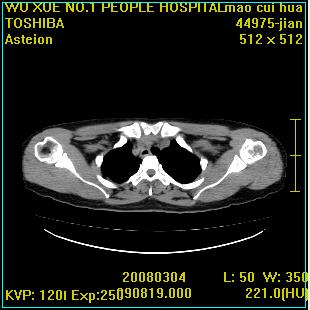

标题: CT12025:男,50岁,左肩活动受限半年。 [打印本页]

标题: CT12025:男,50岁,左肩活动受限半年。

肩关节骨质破坏呈小囊状,其周软组织轻度肿胀,余未见异常。

考虑:肩袖损伤。建议mri。

左侧肱骨头密度不均匀,高低混杂,周围软组织略肿胀,考虑结核性病变。

左侧肱骨头密度不均匀,高低混杂,髓腔密度稍高,周围软组织略肿胀,肌间隙模糊,考虑慢性骨髓炎可能。密切结合临床!